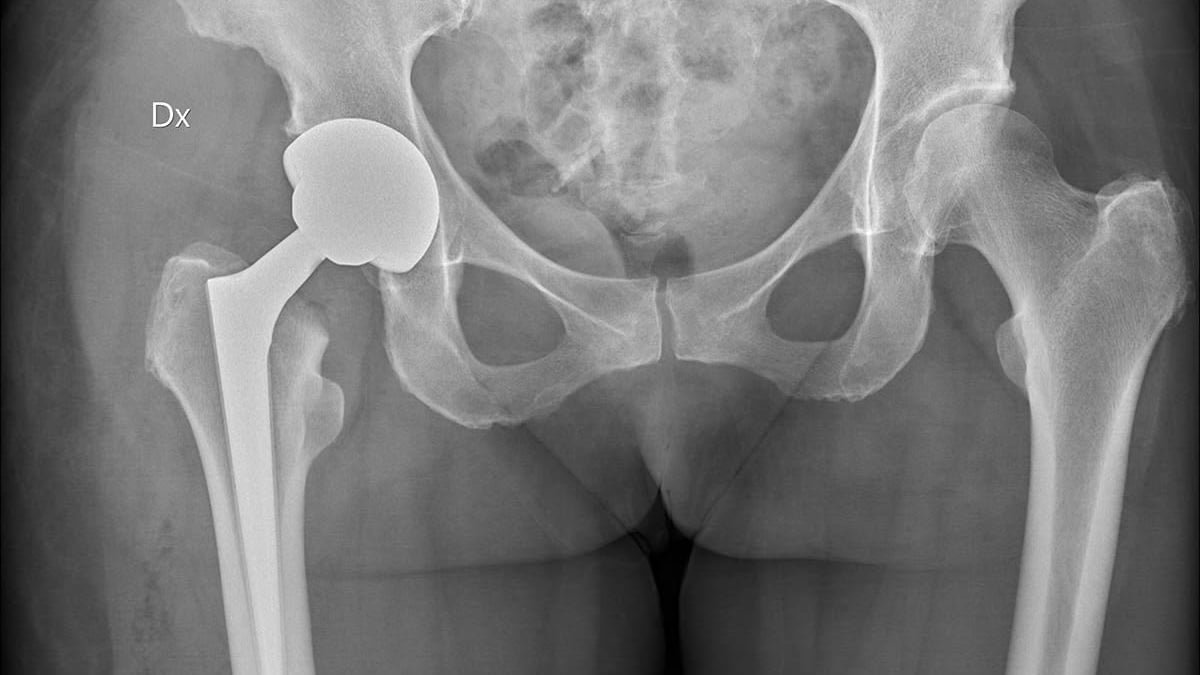

Röntgenbilden visar ett bäcken där patienten på ena sidan (vänster i bild) fått en höftprotes inopererad.